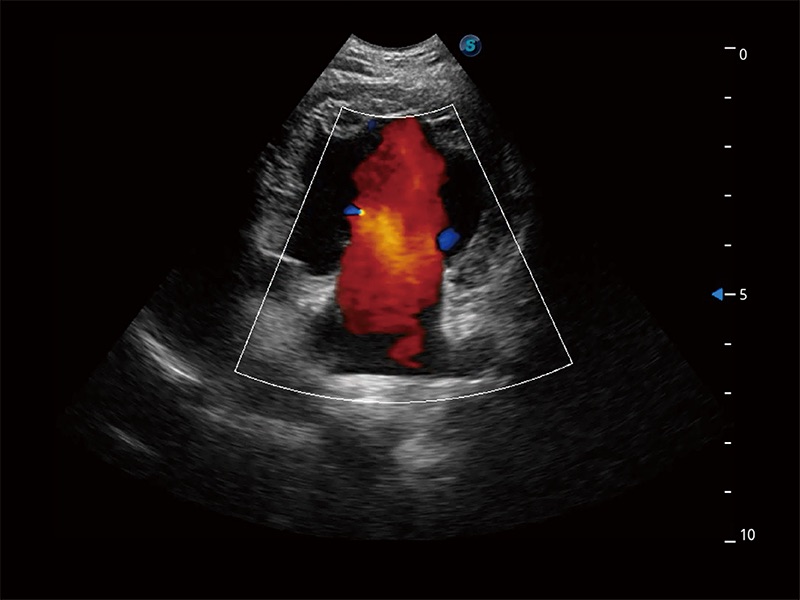

(犬)胎儿主动脉弓立体血流

在传统二维血流成像的基础上,呈现血流的立体感,具有动感的生命力之美。即便是微小的血管也能轻松应对,提高了血流的视觉敏感性。